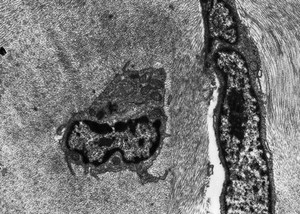

Lymphocyte and keratocyte in corneal stroma. Rob Young. Attribution-NonCommercial 4.0 International (CC BY-NC 4.0). Source: Wellcome Collection.